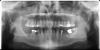

yury59 Опубликовано 8 ноября, 2009 Поделиться Опубликовано 8 ноября, 2009 Ощущение зуба не депульпированного .т.е. живого после его лечения кариеса при приеме пищи теплой, прошу тех , кто разбирается в этой проблеме ответить , -залечил зуб т.е. лечил кариес - до пульпы было далеко -так сказал врач- опытный , но через день при приеме пищи ощущаю зуб т.е. не боль а только чувствую зуб . что это ? спасибо за помощь , посылаю снимок , зуб номер 6 слева вверху на снимке , хотел бы узнать про ощущения зуба после его лечения при приеме пище , это пройдет ? или надо идти к стоматологу для выяснения причины ? неуже ли снова вскрывать плобму ? Ссылка на комментарий